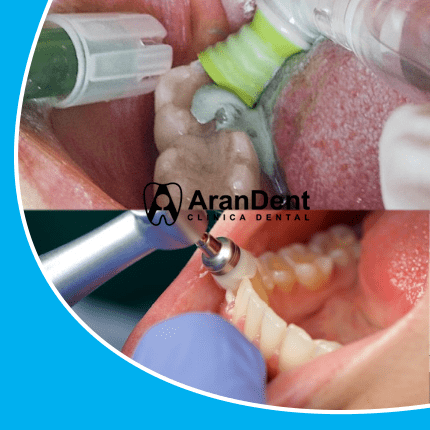

Nuestro trabajo involucra procedimientos que no generen traumas al paciente. Por ello, antes de tomar la decisión de colocarte un implante dental es necesario que estés al tanto de cuáles son los principales beneficios de someterte a este tipo de intervención:

En la actualidad, las coronas que se colocan encima del implante tienen buen acabado estético y gracias a la alta calidad del material, es posible conseguir el tono de tus dientes. / Además, permiten que el paciente pueda disfrutar de sus alimentos, sonreír sin miedo y hablar.